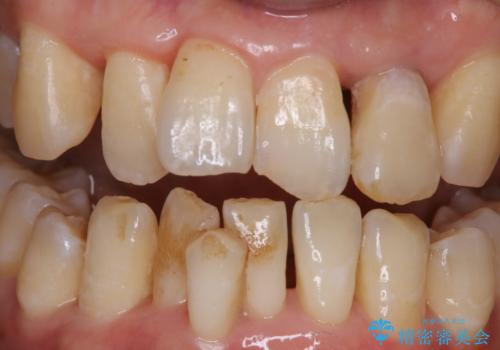

歯周病の治療前にまずはモチベーションUPにPMTCでステインの除去

担当医 歯科衛生士